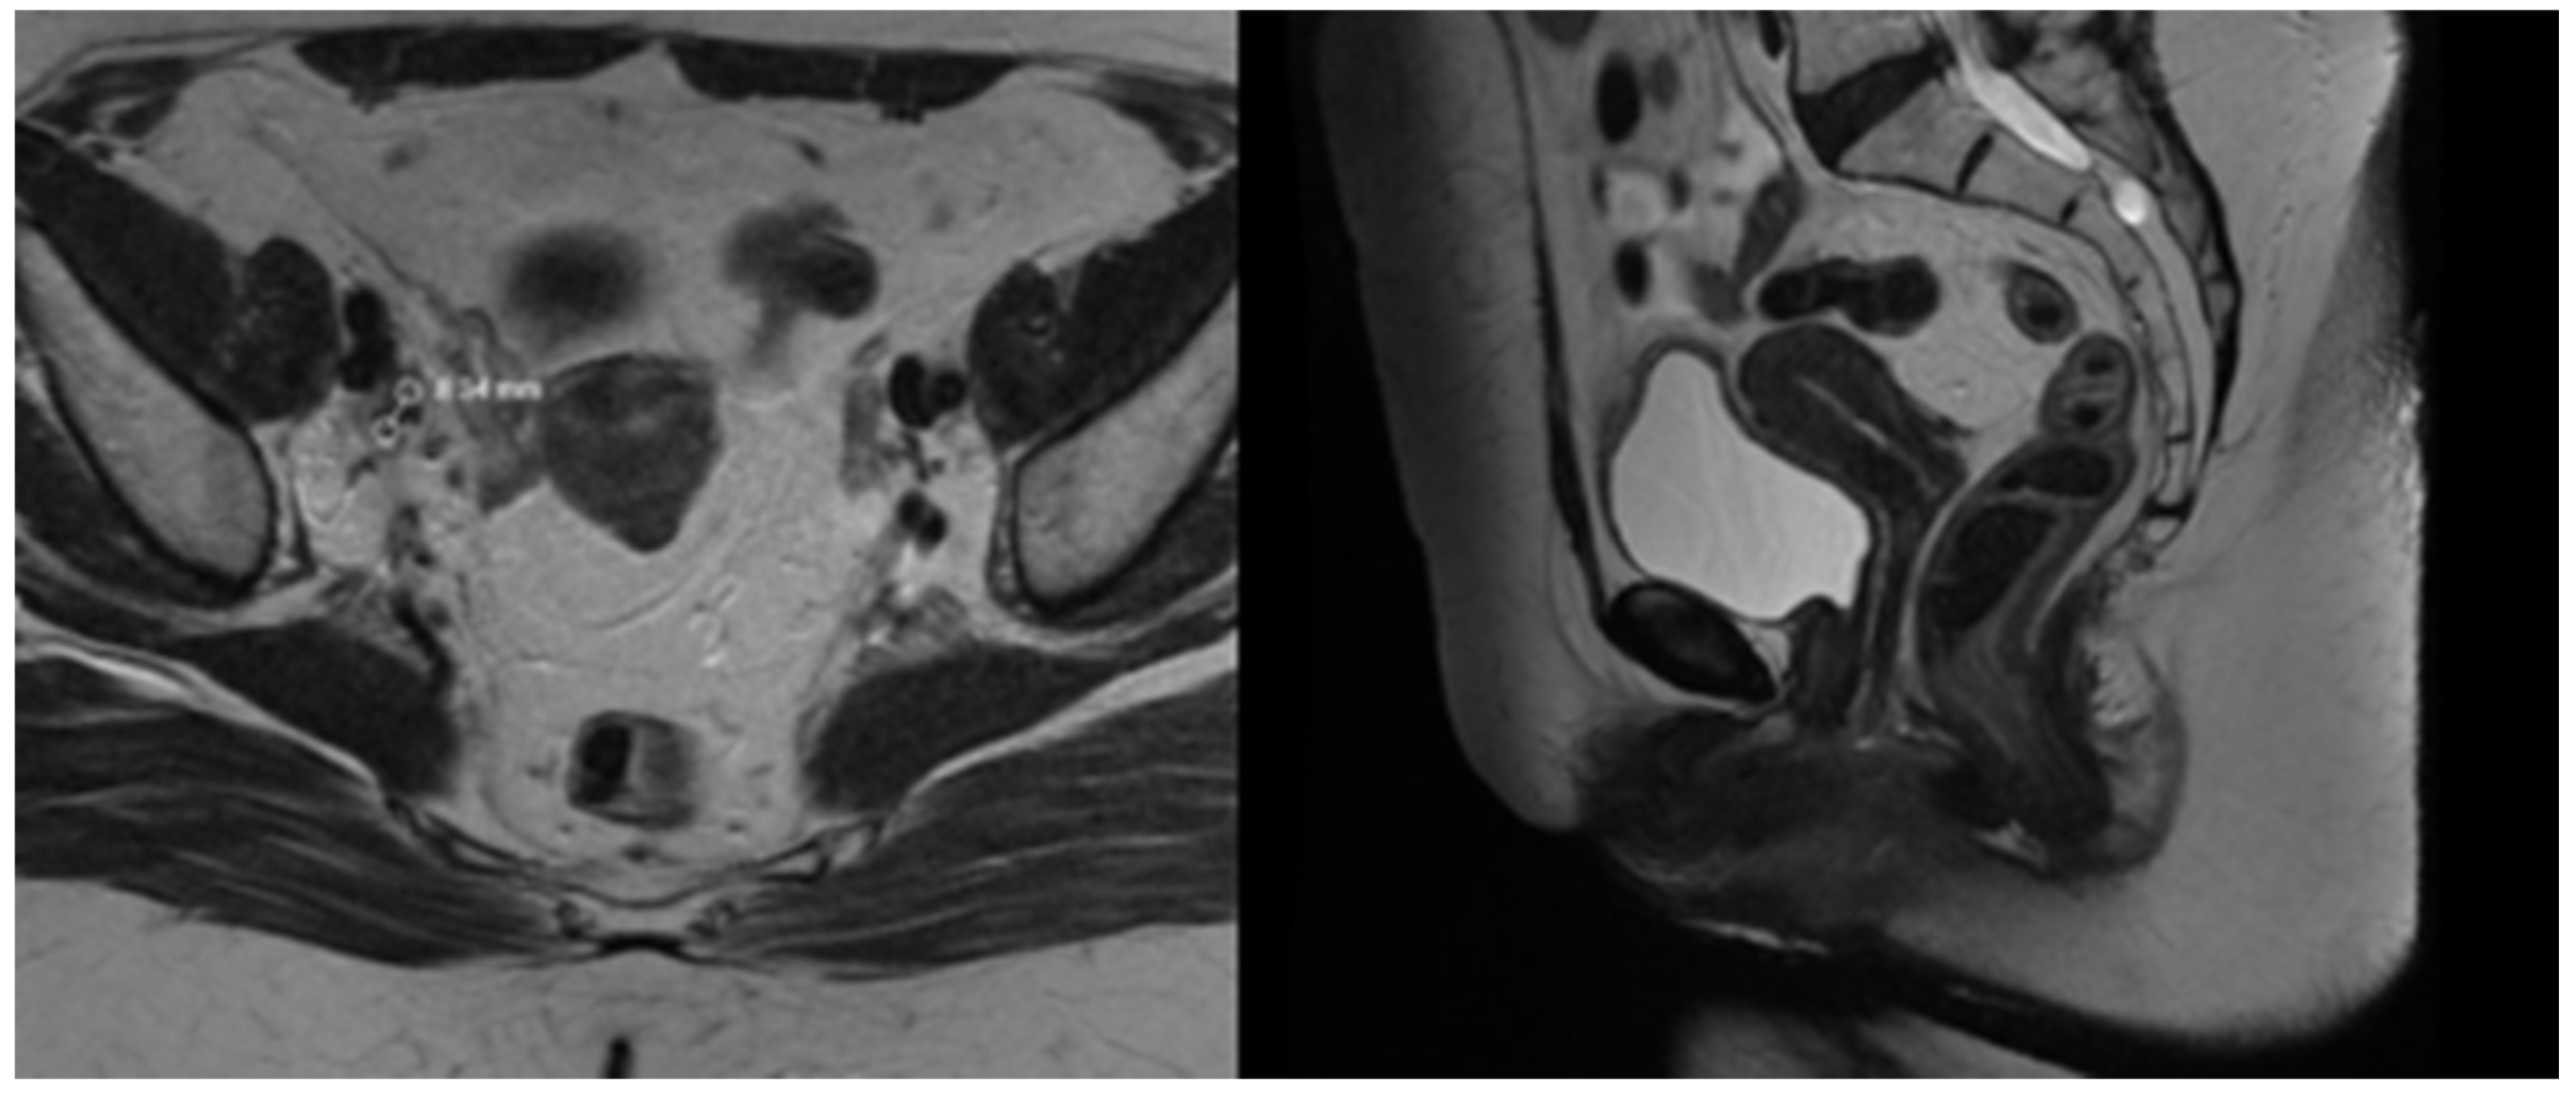

The patient was simulated in a prone position with hands above the head and was immobilized with a thermoplastic mask covering the abdominal and pelvic area. Knee and feet rests were also used for immobilization. Treatment planning computed tomography (CT) protocol included oral administration of 50 mL iodine contrast media in 500 mL of water 30 min before simulation and CT images with 2 mm slice thickness. The treatment planning system (TPS) Monaco 5.1. was used for dosimetric calculation. The contoured organs at risk (OAR) included the small bowel, liver, spleen, pancreas, stomach, spinal cord, kidneys, bladder, rectum, sigmoid colon, skin, and femoral heads and necks. The clinical target volume (CTV) included the uterine body, cervix and parametria, the upper vaginal third, and regional lymph nodes: common, internal, and external iliac, obturator, presacral, and paraaortic up to the renal vessels. The prescribed dose to the planned target volume (PTV) was 45 Gy in 25 fractions, five times a week, with a CTV to PTV margin of 5 mm. The involved lymph nodes received a simultaneous integrated boost dose of 55 Gy in 25 fractions with a 3 mm safety margin from the gross tumor volume to the PTV. Dosimetric planning was performed using a single 360–arc with 6 MV photons. The achieved target coverage was as follows: 95% of the prescribed dose covered more than 95% of the PTVs, and 100% of the prescribed dose covered more than 99% of the CTVs. OARs met both the soft and hard constraints from the EMBRACE II protocol [15] except for the bowel and sigmoid colon, where only the soft constraints were achieved. In this particular case, additional actions were necessary during dosimetric planning to ensure the skin’s minimal radiation exposure. To evaluate skin dose, a structure covering the outer 5 mm of the body surface was created. The maximal skin dose was 34.09 Gy, with 30 Gy in 1.06 cm3, 20 Gy in 53.32 cm3, and 10 Gy in 552.84 cm3 (11.8% of the structure’s total volume). The maximal dose to the pubic skin was 12 Gy. The total and skin dose distributions are represented in Figure 3.

Figure 3.

(Left side): dose distribution from 55 Gy, which is 100% of the prescribed dose (in red) in boosted lymph nodes and 45 Gy (in yellow) prescribed dose in the whole PTV to 10 Gy (in white). (Right side): Three-dimensional reconstruction of the patient’s skin with the distribution of 10 Gy in pink. All regions of existing skin lesions were avoided and received less than 10 Gy.